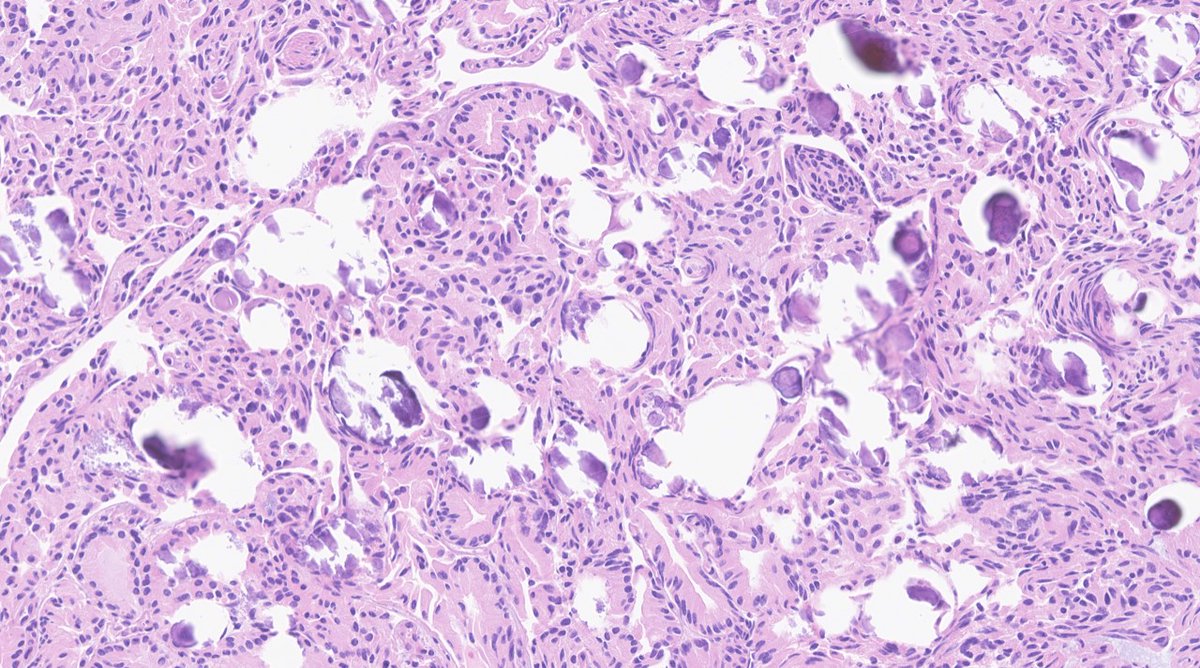

Monday PM 1:45-2:00pm Liver Pathology Platform Session (CC Room 217) #USCAP2023 Dr. Mustafa Arslan MSK Department of Pathology & Laboratory Medicine presents: “Undifferentiated Embryonal Sarcomas of the Liver: Analysis of 18 Adults Cases” #gipath